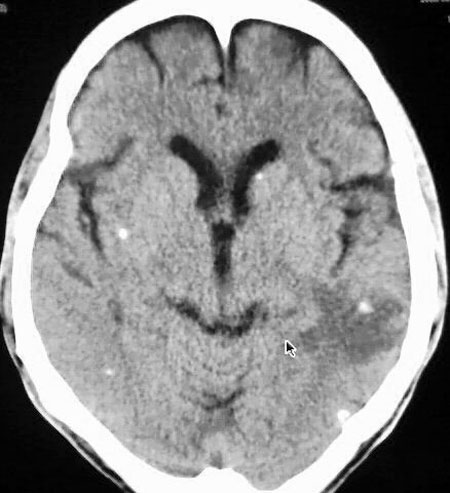

以下是引用守望可可西里在2006-9-6 8:01:00的发言:[br][br] “国内文献进行了脑囊虫病的ct分期:①活动期: ct标志为头节、囊壁、囊液同时存在,分为脑实质小囊型与脑室型;②退变死亡期:ct标志为头节消失、囊腔肿大、虫体崩解,分为单发或多发小囊型、大囊型、葡萄状囊丛型、脑炎型、脑内小脓肿型、脑梗塞型、脑膜炎性③钙化期:标志为囊虫灶转为高密度的钙化结节;④混合期:为活动期、退变期、钙化期病灶混合存在。”[br] 本病例左颞叶、右颞顶叶低密度影,无占位表现,病灶极似脑梗塞。但双侧病灶中偏边缘部位还是有圆形钙化灶,可以考虑为虫体钙化。再加上脑实质内见散在的不对称圆形钙化,其形态类似“大米粒状”,本例应该考虑是脑囊虫病,分期为混合期。